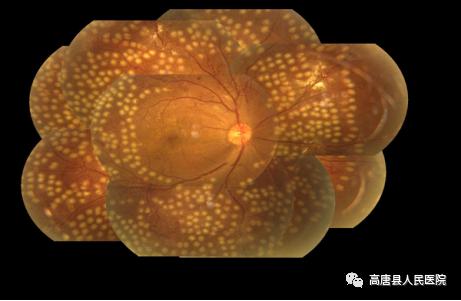

糖尿病视网膜病变的治疗,治疗方法之一是激光视网膜光凝术,将激光束对准新生血管光凝,以破坏新生血管和封闭渗漏的血管。因为视网膜不含感觉疼痛的神经,激光光凝术不会引起疼痛。